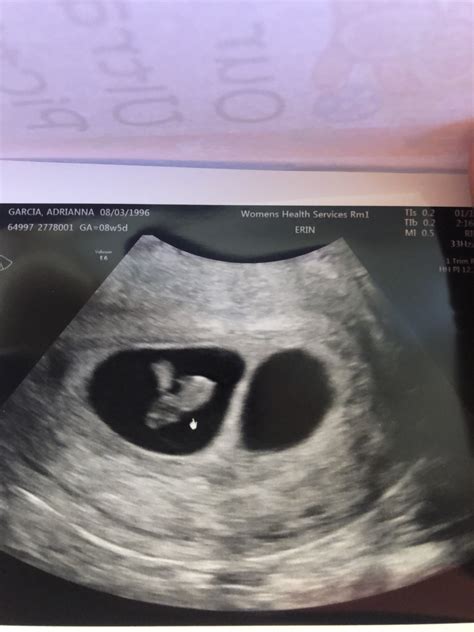

A 6 week sonogram twins is typically the first ultrasound performed during a twin pregnancy. At this stage, the embryos are still very small, but the ultrasound can detect the presence of two gestational sacs, which are the early structures that will develop into the amniotic sacs. This confirmation is essential for early detection and monitoring of twin pregnancies.

• Detection of Gestational Sacs: The primary goal of the 6 week sonogram twins is to detect the presence of two gestational sacs. Each sac contains an embryo and will eventually develop into an amniotic sac.

• Heartbeat Detection: While it is possible to detect fetal heartbeats at 6 weeks, it is not always guaranteed. The heartbeats may be visible as flickering movements within the gestational sacs.

• Measurement of Embryos: The ultrasound technician will measure the size of the embryos to ensure they are developing at the expected rate. This measurement is crucial for assessing the health and viability of the twins.

• Presence of Gestational Sacs: The detection of two gestational sacs confirms a twin pregnancy. This is a crucial finding that sets the stage for ongoing monitoring and care.

• Fetal Heartbeats: If fetal heartbeats are detected, it is a positive sign of viability. However, the absence of heartbeats at this stage does not necessarily indicate a problem, as it may be too early to detect them.

• Embryo Measurements: The size of the embryos will be measured to ensure they are developing at the expected rate. Any discrepancies may require further monitoring or additional tests.